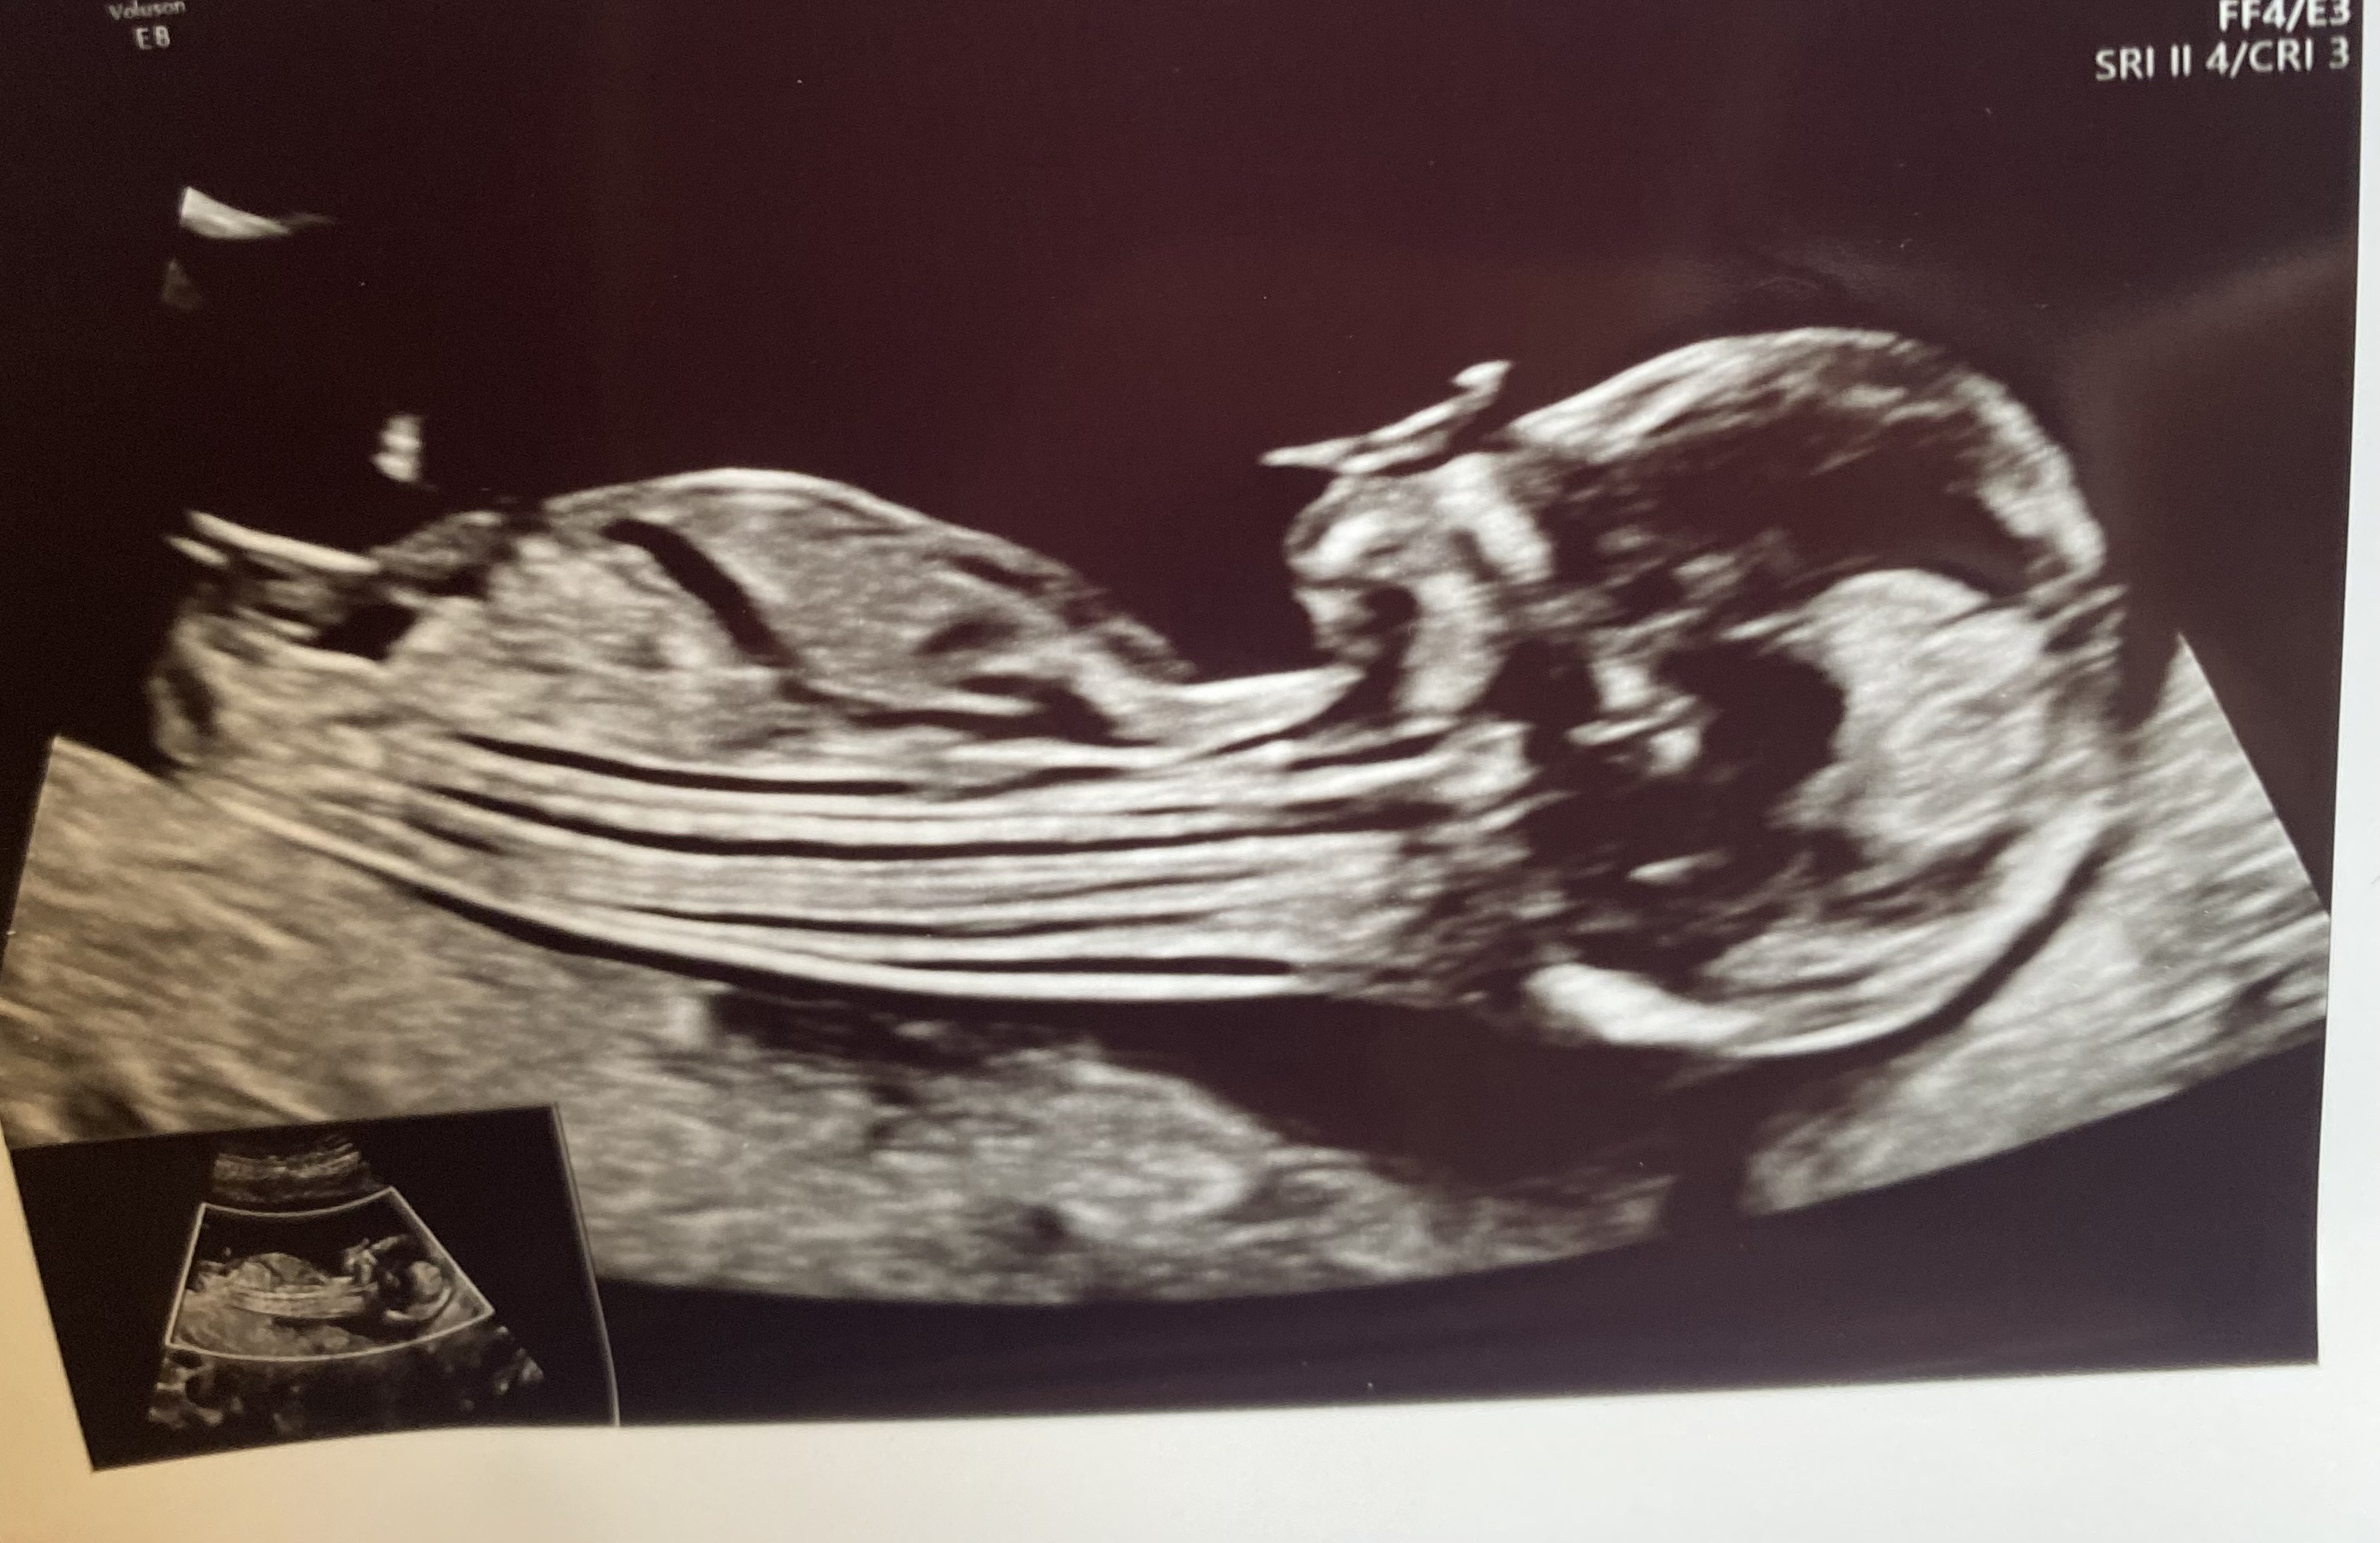

Girl!

Thank you, Atomic. I think you are right, went to another US today at 14+1 and doctor said 90-95% chance of girl :)